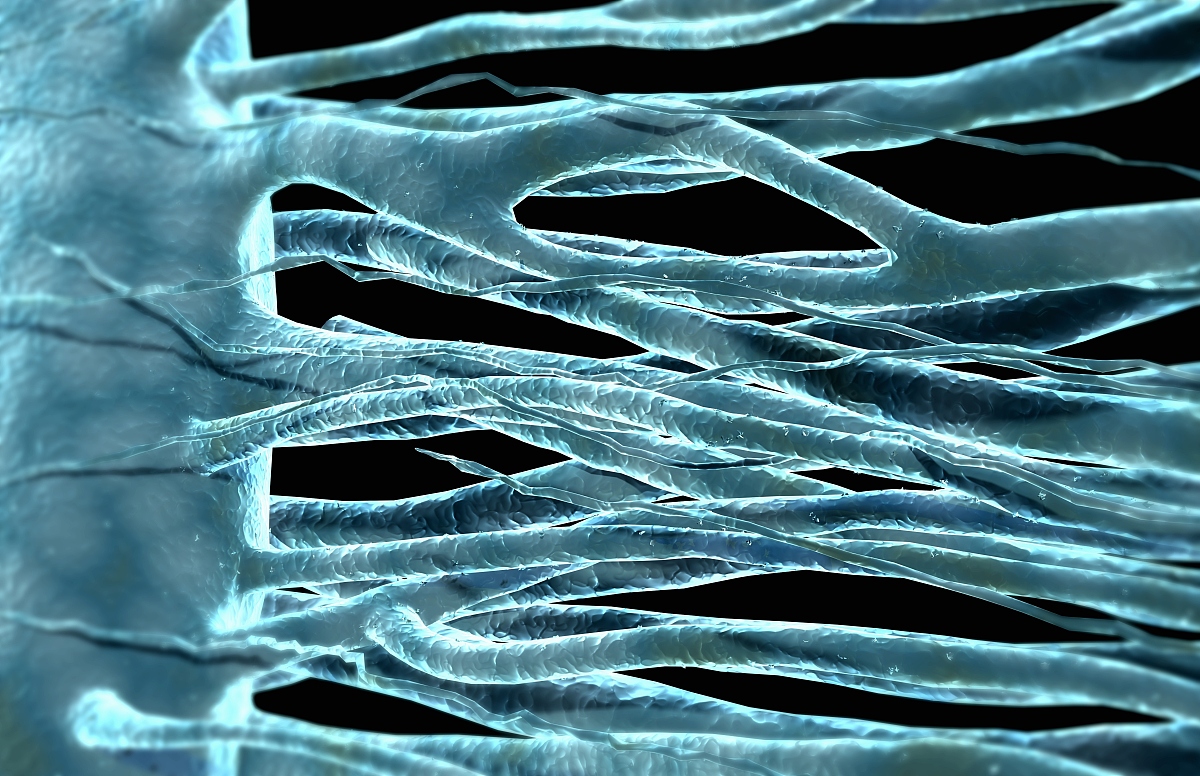

无髓神经纤维图片

无髓神经纤维

图2-31 无髓神经纤维

无髓神经纤维:无髓神经纤维由较细的轴突和包在它外面的神经膜细胞

无髓神经纤维: (1)周围神经系统的无髓神经纤维 : 特点: 施万c长柱状